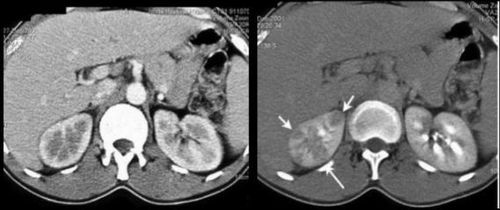

Hình ảnh viêm thận - bể thận sinh hơi trên cắt lớp vi tính

Viêm thận - bể thận sinh hơi là căn bệnh ít được mọi người biết đến, các trường hợp phát hiện ra bệnh thường quá muộn và phải điều trị bằng phẫu thuật cắt bỏ thận. Chụp CT là phương pháp hiệu quả và nhanh chóng giúp bác sĩ đánh giá được tình trạng bệnh kịp thời.